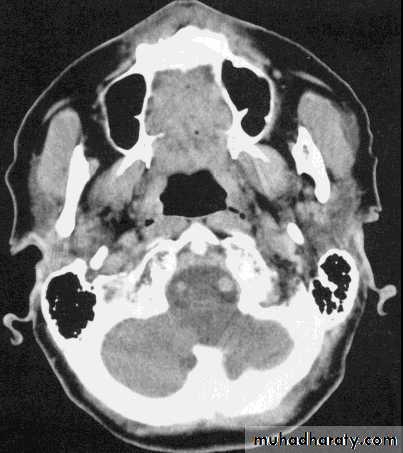

ComparisonsMRI image

CAT image

head

Compare bone and soft tissue density